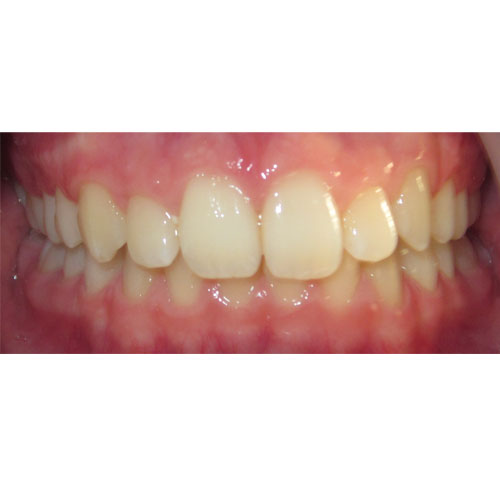

Nasze rezultaty